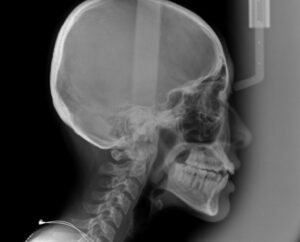

次に前歯の 出っ歯を調べる

セファロというレントゲン撮影

以上の資料から

歯科医が治療計画を立てる